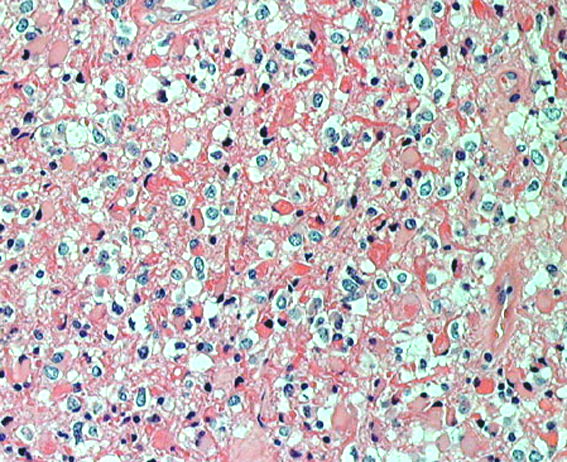

HE染色では,perinuclear haloをもった小型の腫瘍細胞が見られ,また右ではminigemistcyteと呼ばれる小さいけれどeoginophiricな胞体の豊かな腫瘍細胞の出現があり,典型的な乏突起膠腫の像です。

左に細かい石灰化が見られます。右は,グレード2の乏突起膠腫には珍しい血管内皮の増生 gromerulation なのですが,必ずしも悪性像とはいえません。通常の乏突起膠腫と同様にchicken wireと呼ばれるような細かい腫瘍血管網も存在しました。